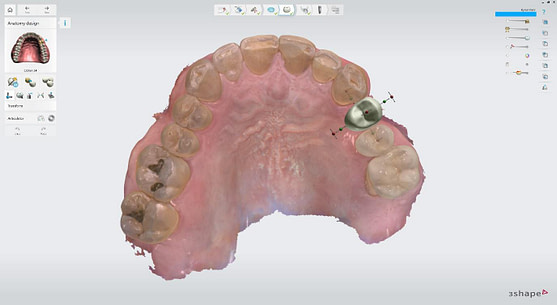

I utilized 3Shape Implant Studio, a module within the 3shape Unite Platform, to plan and execute the surgical procedure.

Pre-surgical planning began with acquiring high-quality diagnostic data, including TRIOS intraoral scans and CBCT imaging. The data was imported into 3Shape Implant Studio, where I designed a virtual crown for tooth 24 and planned the precise positioning of the implant, considering critical factors such as sinus proximity, adjacent roots, bone density, and the location of the bony defect.

Digital impressions were captured using the TRIOS 4 intraoral scanner, and the implant-supported crown was designed using 3Shape Design Studio.

Implant detection matches the scan body in the intraoral scan with the digital library. A colour scale is given to show the accuracy of the matching (Green is good).